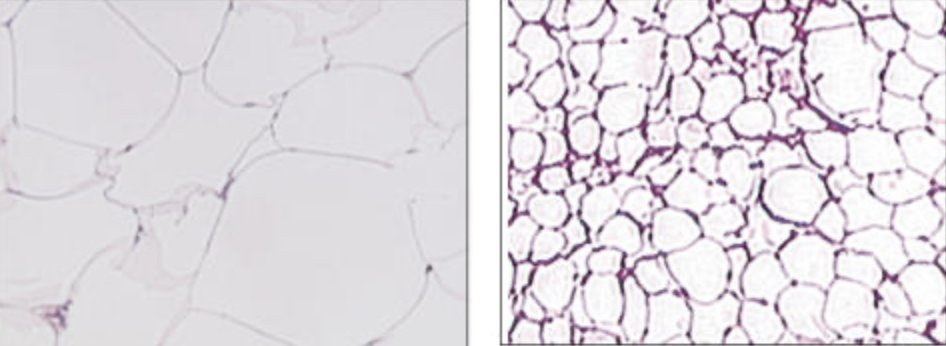

How we store fat matters more than how much fat we store. This idea emphasizes the importance of the size of each individual fat cell, rather than the total mass of the fat. This image compares fat cell size of South Asian men (left) and Caucasian men (right). Note the incredible